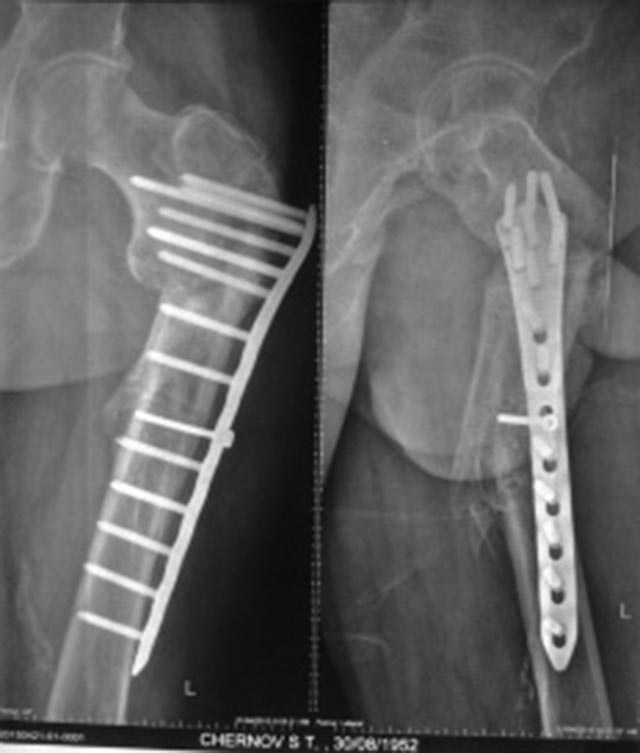

Мужчина 63 года, травма в феврале 2013 г. - перелом в/3 левой бедренной кости. В ЦРБ остеосинтез пластиной LCP. 17.06.2014 г. пластина удалена, стал отмечать боли, патологическую подвижность в бедре, укорочение левой нижней конечности на 4 см. 04.02.2015 г. в одном из учреждении г. Москвы произведена резекция ложного сустава, остеосинтез пластиной с пластикой Коллапаном. На сегодняшний момент беспокоят боли и патологическая подвижность в области верхней трети левого бедра, укорочение конечности на 4 см, передвигается при помощи костылей с нагрузкой на оперированную конечность. Рентгенограммы от 21.04.2015 г. и 16.08.2015 г.В отделении планируется: удаление пластины, остеотомия, восстановление ШДУ, фиксация стержнем. Вопрос: возможно ли выполнить операцию одномоментно или необходимо аппаратное удлинение бедра?

Да уж оба раза поработали "спецы". Снимок не очень что-то. По тому что рассмотреть удалось- вроде можно одномоментно. Стержень надо попрочнее, ШДУ чуть в вальгус. Удостовериться в отсутствии инфекции.

План вполне рациональный, но лучше бы увидеть схему того, что предполагается сделать. Где остеотомию, как будут располагаться отломки.

Чтобы ответить насчет длины - надо иметь что-то для измерений. Или снимок обеих нижникх конечеостей на одной пленке, либо можно уложить пациента на спину, выровнять таз, сделать снимки обоих проксимальных бедер на одной пленке, и обоих коленок на другой, не меняя положение пациента. Тогда будет хорошо видна разница длин, и будет понятнее, что получится от одной угловой коррекции.